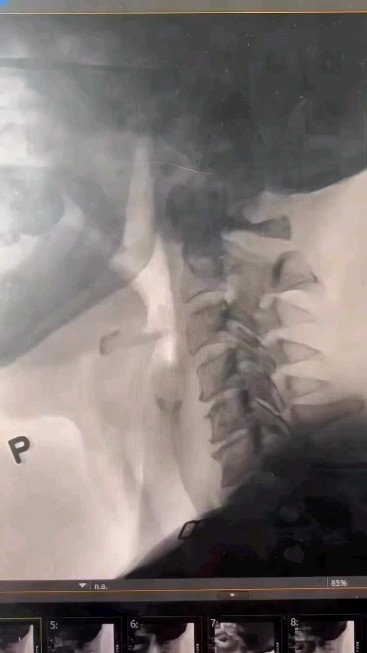

This little lady is 11 years s/p XRT to her oral and Q base of tongue as well as a partial hemiglossectomy. No surprise to see all that bass of tongue residue once I found out she received 238 Gy in 36 fractions. To compare, a more typical dose today would be 66 Gy in 35 fractions. Follow us for more @medicohubworldwide Tag your friends #oncology #medicaldiary #cancer #oncologia #cancerawareness #breastcancer #cancersurvivor #health #chemotherapy #cancercare #cancertreatment #medicine #cancersucks #covid #oncologist #cancerresearch #cancerfighter #healthcare #cancersupport #doctor #surgery